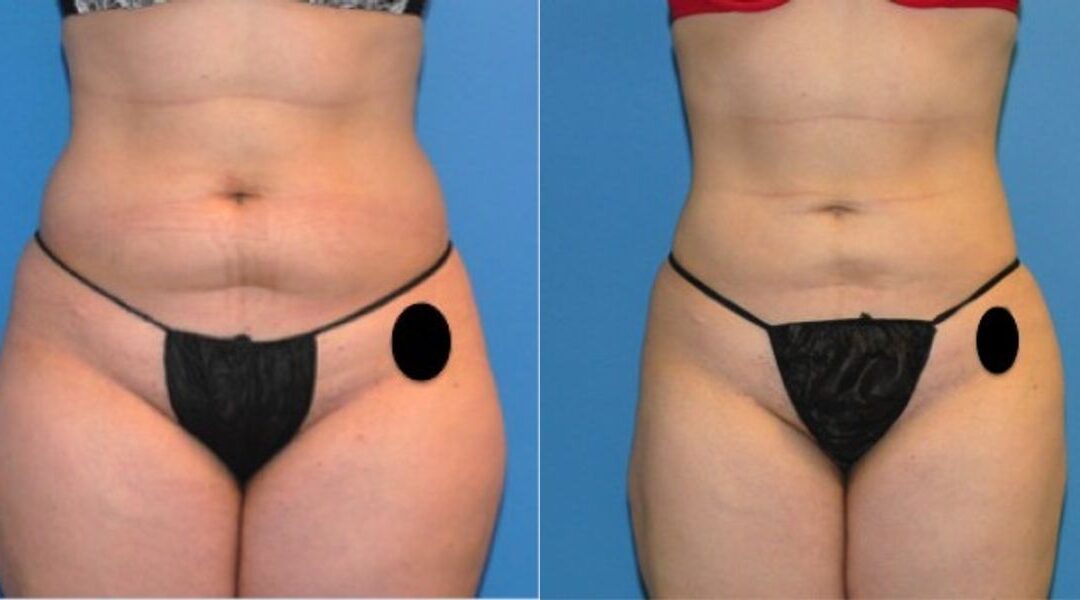

This patient desired improvement in the mild fattiness that she had along the abdomen and waist regions. She is an excellent liposuction candidate because of her youthful and elastic skin quality. She was treated with tumescent liposuction to the upper and lower abdomen, waist and hips. Her post operative result is depicted at one year after surgery, when all of the post operative swelling common with liposuction has resolved. Her cosmetic result is smooth and uniform with good improvement in the treated regions.